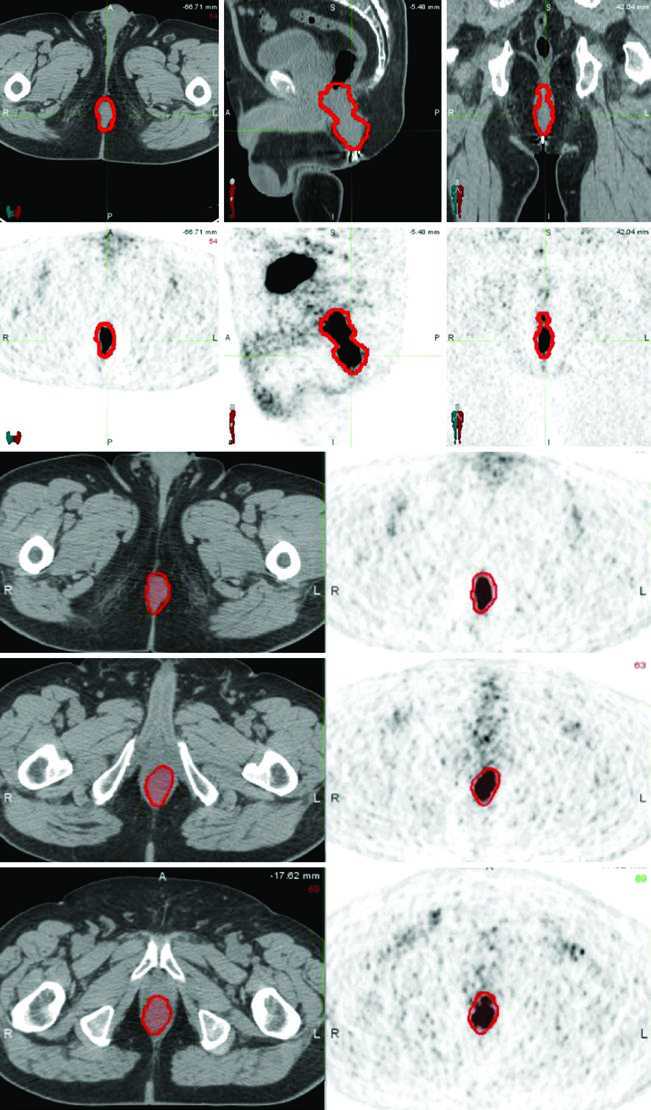

PET/CT is recommended for both staging and treatment planning to help delineate the extent of gross disease. However, areas of low uptake on PET should not supersede physical examination findings or abnormalities seen on CT or MRI. Multi-modality image integration remains the safest approach.

CT simulation with intravenous contrast and slice thickness of 3 mm or less is required to delineate the pelvic blood vessels and gross tumor volume. When available, PET/CT fusion or MRI can significantly assist in target volume definition.

The T2N0 case demonstrates definitive chemoradiotherapy with IMRT: PTV-LR and PTV-HR treated simultaneously to 40 Gy (1.6 Gy/fraction) and 45 Gy (1.8 Gy/fraction) in 25 fractions, respectively. Then PTV-P received a sequential boost to 50.4 Gy (1.8 Gy/fraction) in 28 total fractions.

The T3N1a case with bilateral inguinal involvement had PTV-LR and PTV-HR treated simultaneously to 40 Gy and 45 Gy in 25 fractions. The bilateral inguinal and external iliac nodes were included in CTV-HR due to bilateral inguinal involvement. PTV-P and PTV-N then received a sequential boost to 54 Gy in 30 total fractions.